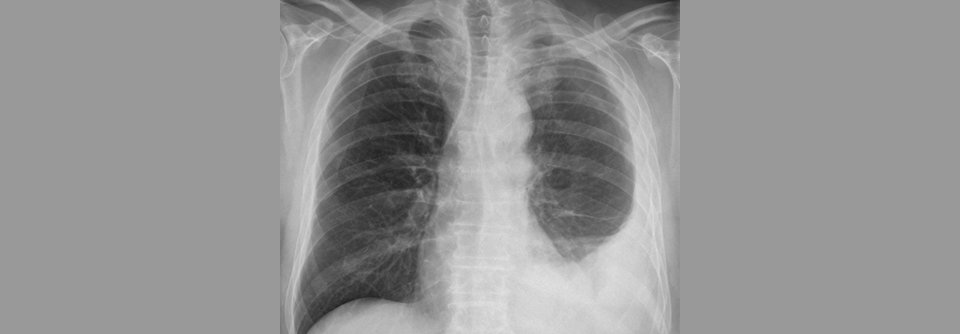

Immuncheckpoint-Inhibitoren haben sich bei der Behandlung des nicht-resektablen Pleuramesothelioms weitgehend bewährt. Immuncheckpoint-Inhibitoren haben sich bei der Behandlung des nicht-resektablen Pleuramesothelioms weitgehend bewährt. © chokniti – stock.adobe.com

In der Therapie des malignen, nicht-resektablen Pleuramesothelioms steht eine neue Therapieoption in den Startlöchern. Immuncheckpoint-Inhibitoren haben sich auch in dieser Indikation als effektiv erwiesen.

Das maligne Pleuramesotheliom ist ein hochaggressiver, zum Diagnosezeitpunkt meist inoperabler Tumor. Weniger als 10 % der Betroffenen überleben länger als fünf Jahre. Bis vor Kurzem stellte die Chemotherapie mit einem Platin plus Pemetrexed den Standard in der Erstlinie dar. Im Oktober vergangenen Jahres wurde zumindest in den USA die Kombination zweier Immuncheckpoint-Inhibitoren, Nivolumab plus Ipilimumab, für die Behandlung des nicht mehr resezierbaren Tumors zugelassen. Beide Antikörper hatten sich im Rahmen einer Phase-3-Studie bezüglich der Überlebensprognose als überlegen erwiesen.